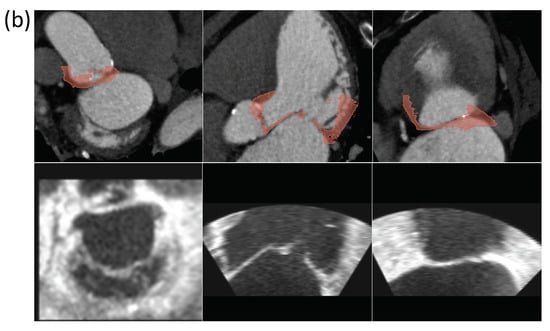

3.1. Case Study 1: Landmark Registration in Cardiology

3.1.2. CT/US Spatial Registration

3.1.3. Landmark Registration Optimization

4.1. Case Study 1